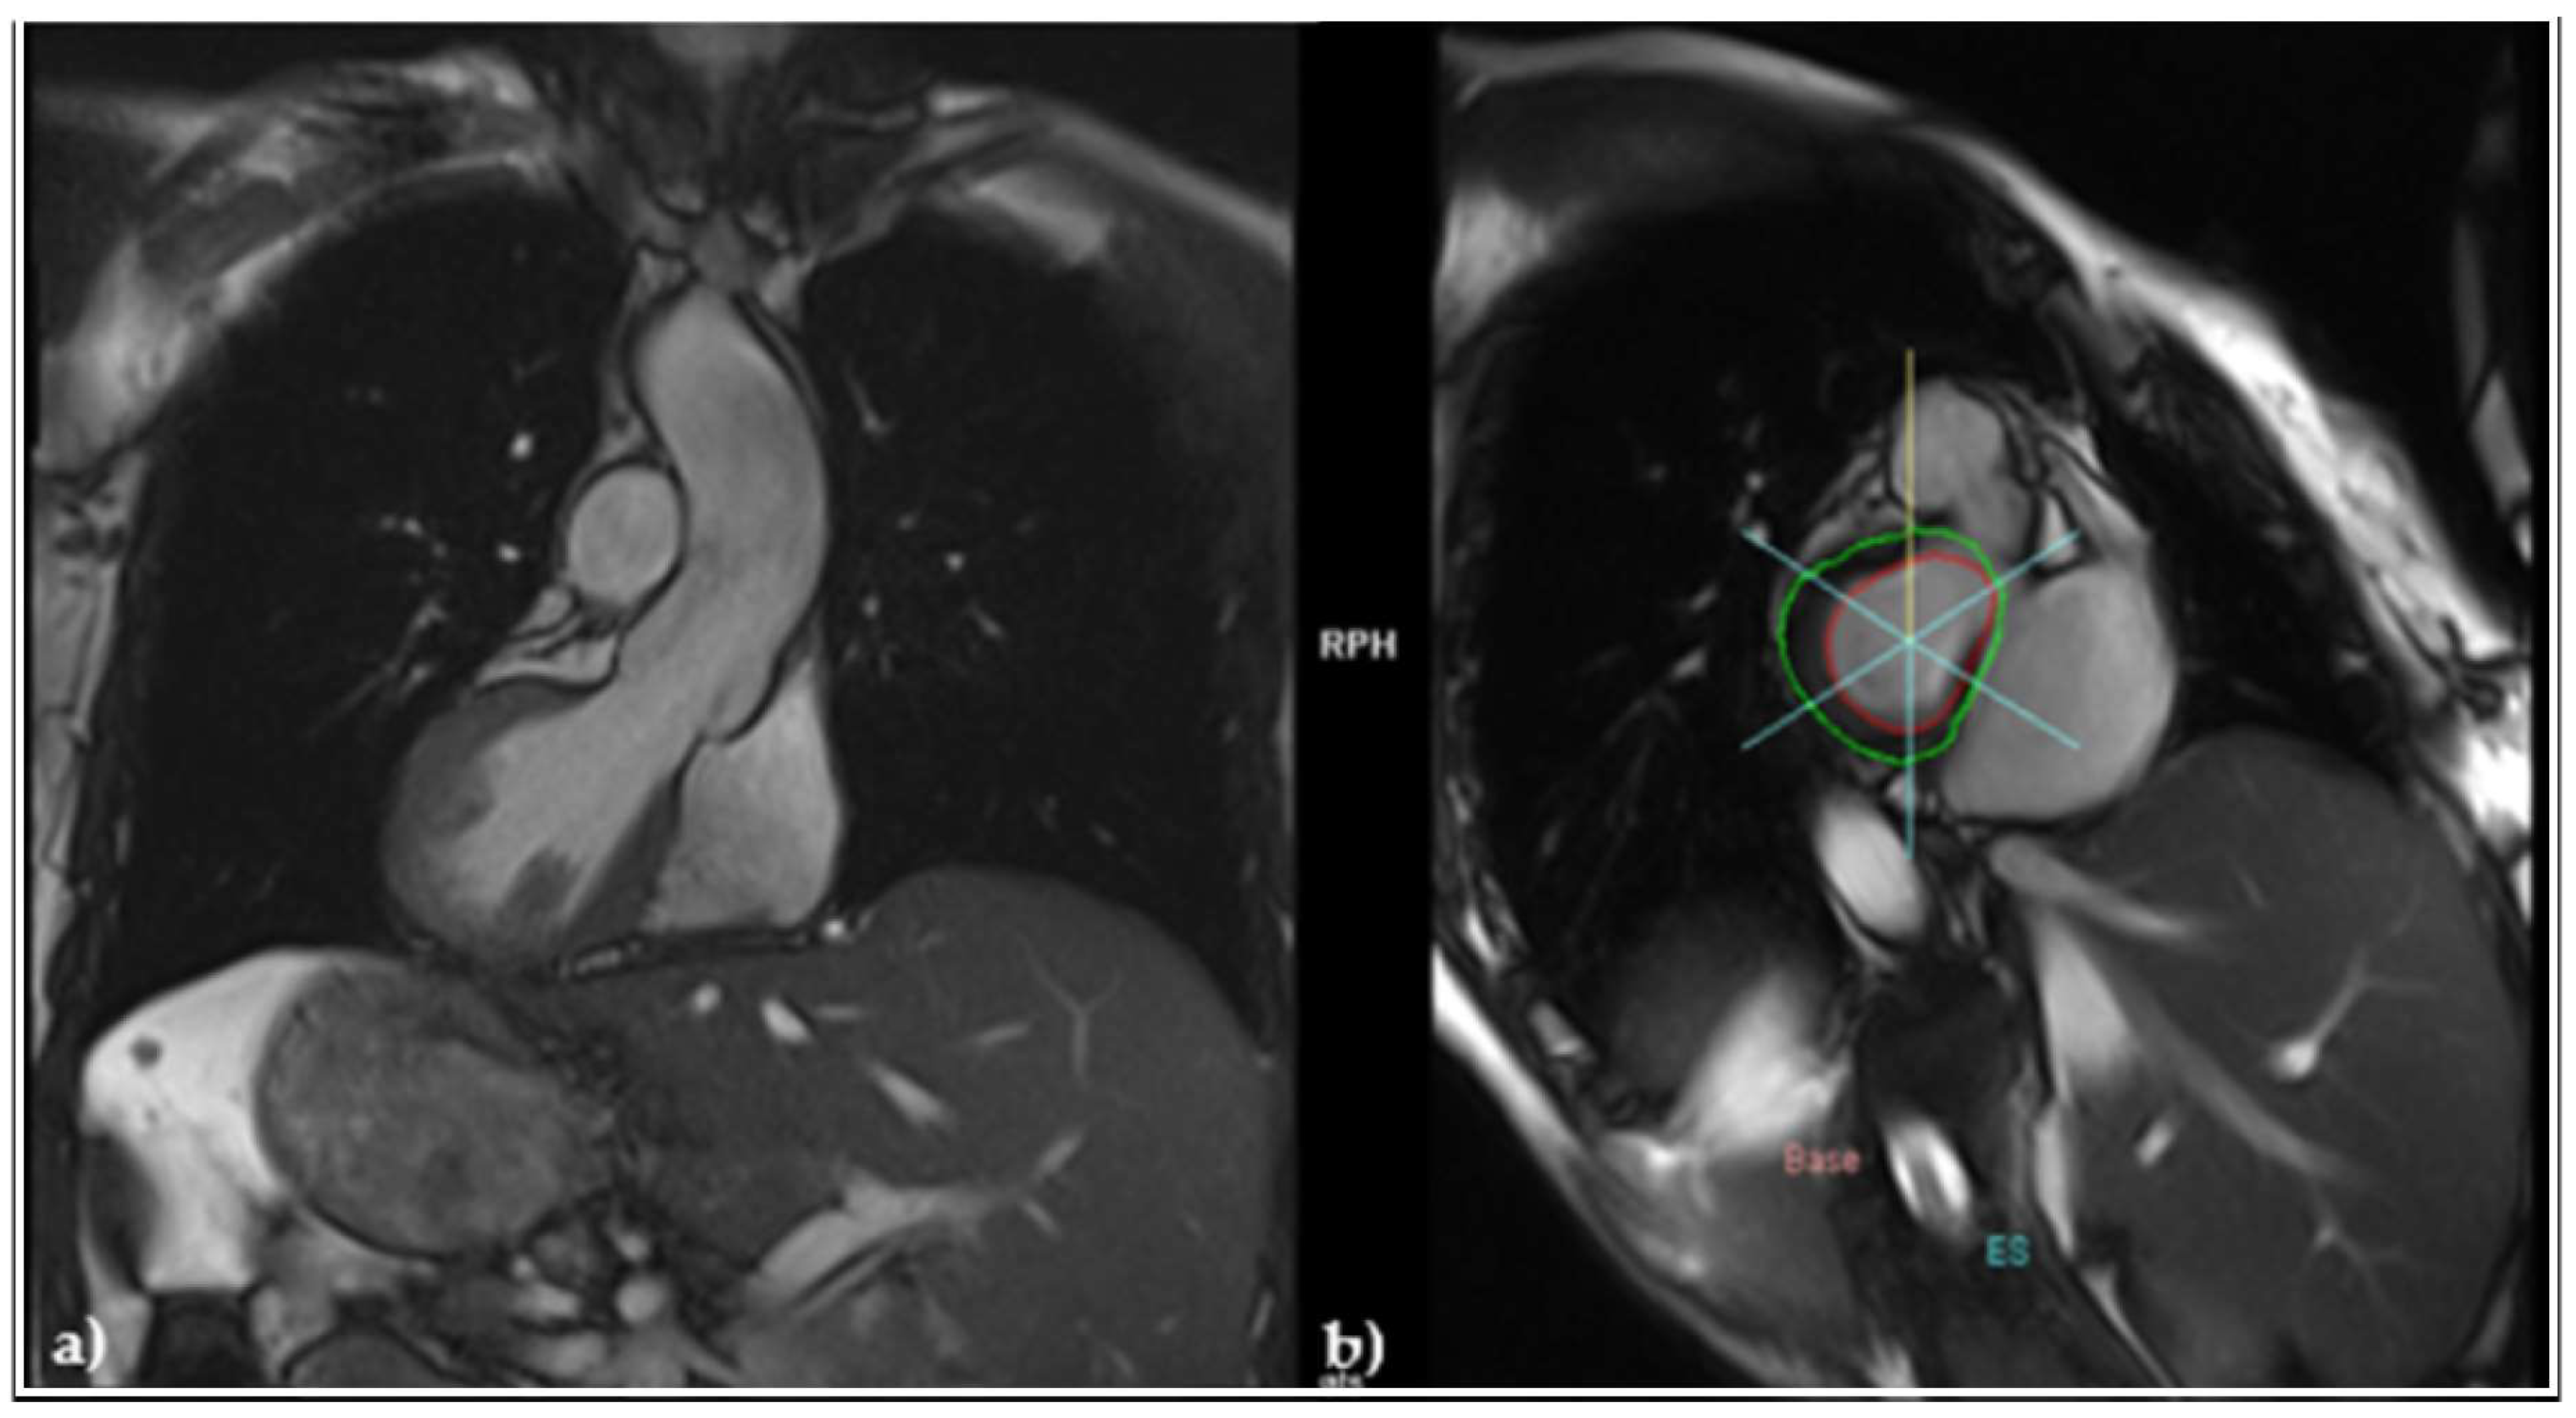

2.2. Diagnostic of SSS and Pacemaker Implantation

2.3. Evaluation of VA, Antiarrhythmic Therapy with Amiodarone and Secondary Effects